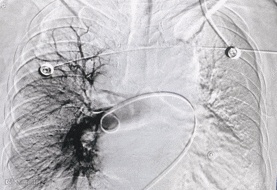

常规消毒铺巾,局麻后穿刺右股静脉成功后,置入血管鞘,行肺动脉造影术,提示右肺动脉上叶支主干栓塞。

术前造影